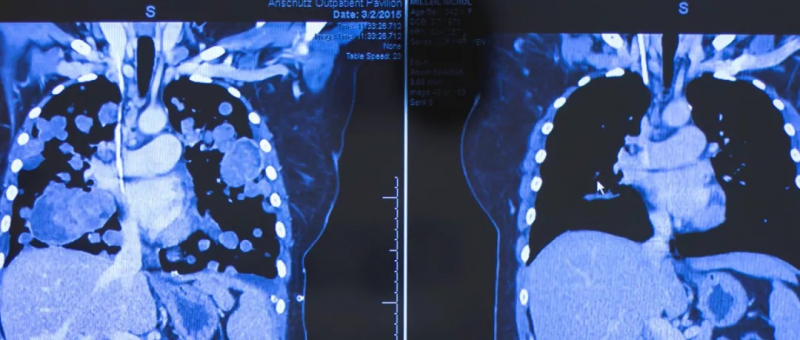

骨与软组织肉瘤专家会诊,中美专家联合会诊为肉瘤患者制定新的治疗方案在所有的实体肿瘤中,骨与软组织肉瘤是相对罕见和特殊的一类恶性肿瘤,发病率仅占实体瘤1%,但病理类型非常复杂,因此确诊和治疗都十分棘手。20岁,确诊为晚期骨肉瘤。。。2018年,M女士出现左侧膝盖的疼痛,贴膏药缓解后就没太在意。但是在一次运动中,M女士左股骨出现了剧烈疼痛,无法受力,到医院详细检